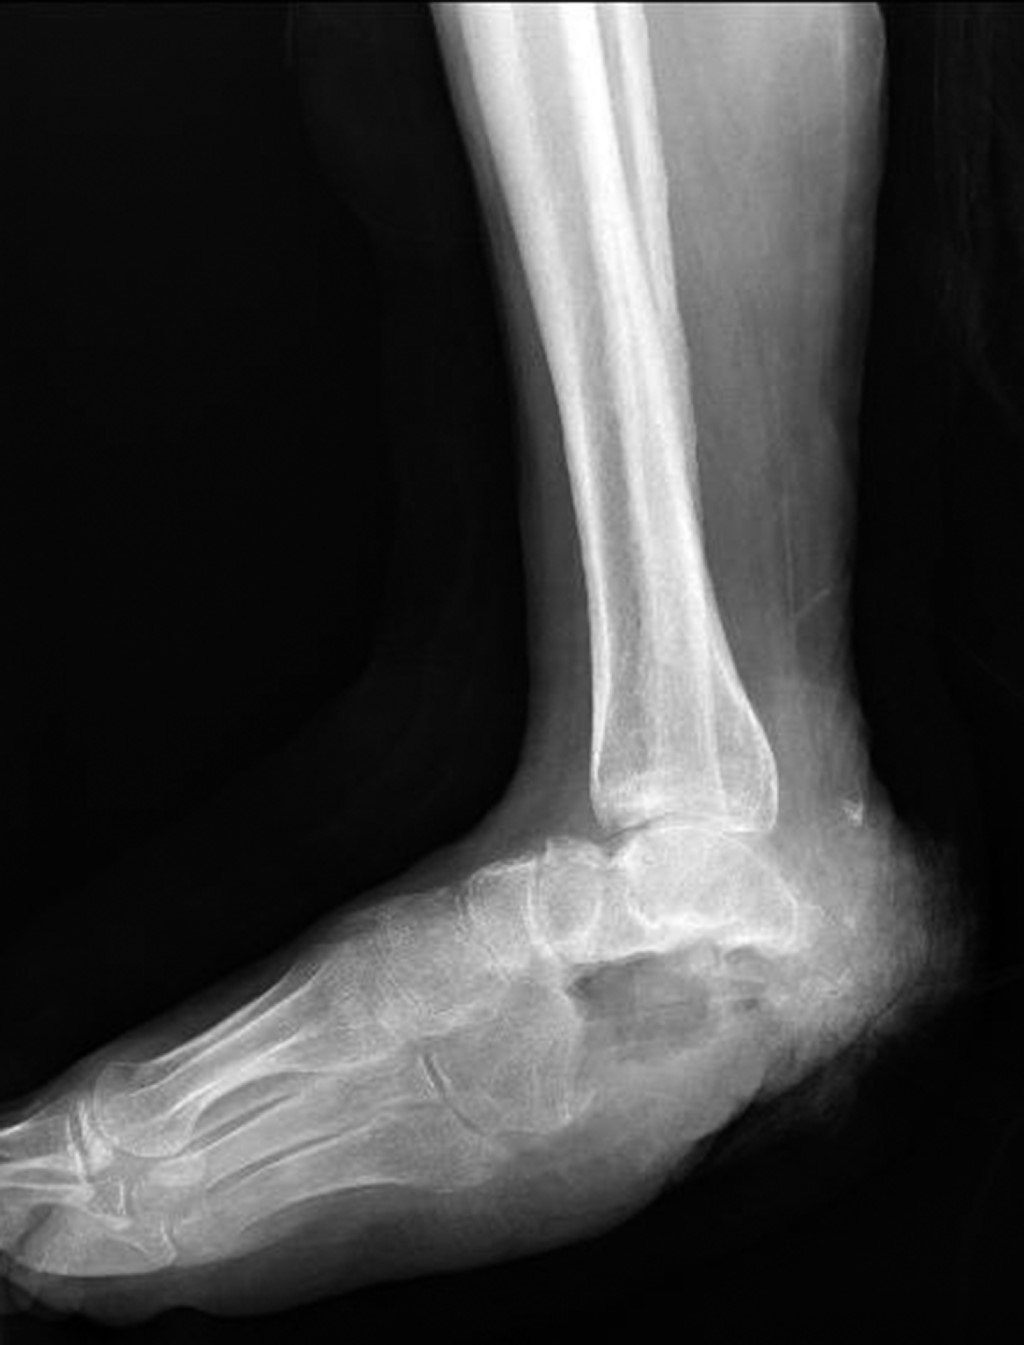

Chronic osteomyelitis of calcaneus: a case report and literature review

We present the case of a 38-year-old male patient at the Miguel Hidalgo Hospital Centenario, Aguascalientes, Mexico, with a five-year history of chronic ulcer on the right heel after direct trauma with a sharp object to the involved heel, with history of flap advancement five years ago. Clinical examination with 7 × 5 cm skin loss with purulent exudate and radiological examination revealed an image of hypotrophy of the right calcaneus with sclerosed bone remains and data suggestive of chronic osteomyelitis. After a first intervention with a polymethylmethacrylate + gentamicin cement spacer with a chain technique and calcaneal curettage, as well as taking a culture, the diagnosis was confirmed with isolation of the Escherichia coli lesion and Enterococcus faecalis, but the spacer was rejected, he intervenes again for calcaneal resection. When the wound heals, ankle foot orthosis is indicated and walking is started without pain, and without recurrence of osteomyelitis.

Figure 2